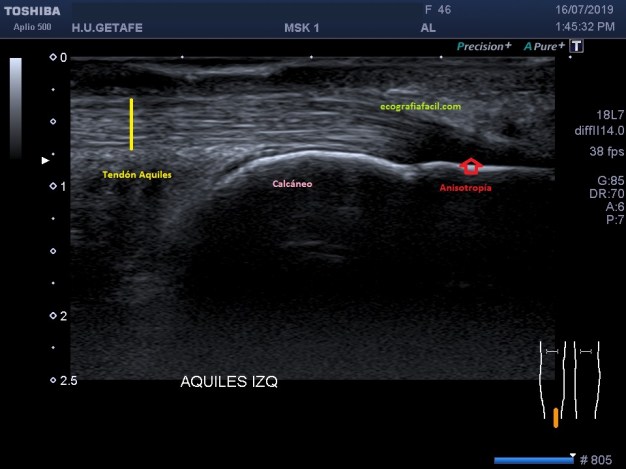

En la imagen número 1 podemos ver una imagen bastante habitual en el estudio del aquiles, marcado con flecha roja, vemos una zona de hipoecogenicidad que corresponde al cambio de angulación de las fibras que en la zona de inserción se objetivan claramente hipoecogénicas en relación con anisotropía.

La afectación tendinosa del Aquiles cursa ecográficamente con cambios hipoecogénicos y de aumento del tamaño como puedes ver en la imagen 6 y 7, respecto de la normalidad, que vemos en la 4 y 5.